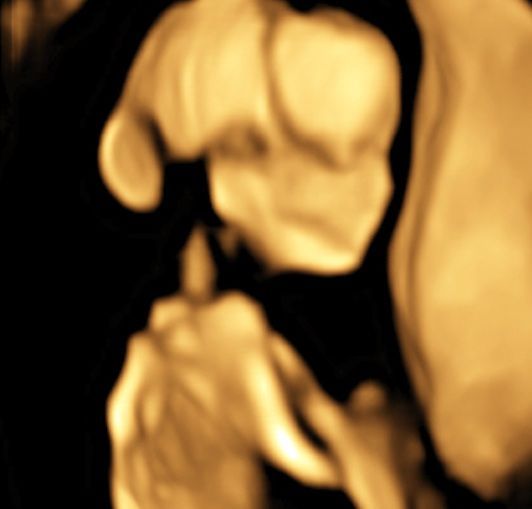

Realizamos las ecografías de viabilidad del embarazo, genética, morfológica, de bienestar fetal, ecocardiografías fetales, así como procedimientos invasivos como biopsia de vellosidades coriales y amniocentesis.